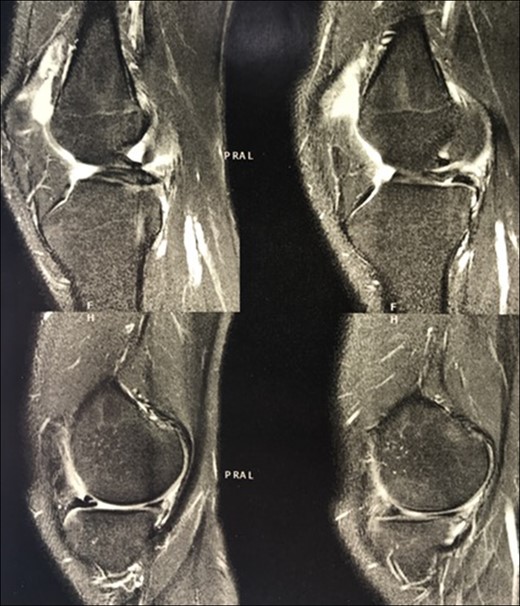

Magnetic resonance imaging (MRI) also showed bucket handle tear of the medial meniscus, complete absence of ACL and PCL, joint effusion, patellofemoral dysplasia, lateral patellar tilt and superficial patellar chondropathy (Fig. 2).

MRI of the affected knee showing the congenital absence of the cruciate ligaments (circles) and the presence of a bucket handle tear of the medial meniscus (arrow).